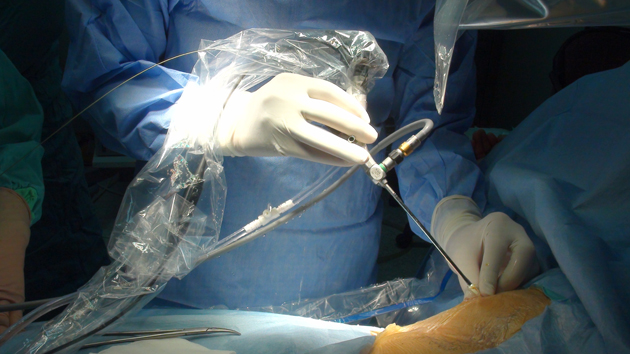

Hastanenin Cerrahi Tıp Bilimleri Üroloji Anabilim Dalı Öğretim Üyesi Prof. Dr. Ahmet Öztürk, Genel Cerrahi Anabilim Dalı Öğretim Üyesi Prof. Dr. Metin Belviranlı, Girişimsel Radyoloji Uzmanı Yrd. Doç. Dr. Süleyman Bakdık ve üroloji doktorlarından Yrd. Doç. Dr. Mehmet Giray Sönmez'den oluşan ekip, ultra mini cihazlarla karaciğere müdahale ederek taşları temizledi.

Operasyonu gerçekleştiren ekipten Prof. Dr. Ahmet Öztürk, yaptığı açıklamada, ameliyatı ekip çalışması sayesinde başarıyla gerçekleştirdiklerini söyledi.

Genel bir değerlendirme sonrası açık ameliyattan ziyade endoskopik yöntemlerle taşın kırılması gerektiği fikrinin oluştuğunu aktaran Öztürk, karaciğerde irili, ufaklı taşlar olduğu için ameliyatın neredeyse imkansız olduğuna işaret etti.

Endoskopik yöntemle karaciğer içerisindeki safra kanalına girerek taşların parçalandığını, bir kısmının dışarıya ve bağırsağa itilerek müdahalenin tamamlandığını anlatan Öztürk, şöyle devam etti:

"Karaciğer çok kanamalı bir organ. Kanallar küçük. Buradaki işlemler tahribata neden olabilir. Bizim kullandığımız aletlerle kanallarda rahat hareket edip, taşa ulaştık. Kanama ihtimalini en az düzeye indirdik. Ameliyattan sonra açılan delik daha çabuk kapandı. 'Ultra mini' diyebileceğimiz yaklaşık 2,6 (8F) milimetrelik aletleri kullanarak müdahaleyi yaptık. Yurt dışında daha kalın, yaklaşık 1 santimetreye yakın aletlerle yapılmış ender uygulamalar var. Biz ultra mini dediğimiz aletlerle bu işi dünyada ilk yapan klinik olmanın gururunu yaşıyoruz. Şu anda ameliyat görüntülerini hazırlıyoruz. Uluslararası camiaya bunu duyuracağız. Video sunumlarla uluslararası toplantılarda uygulamayı anlatacağız. Endoskopik taş tedavisi tecrübemizi karaciğerdeki taşa uyguladık. Sonuçta hastamızın da bizim de yüzümüz güldü. Hepimiz mutluyuz."